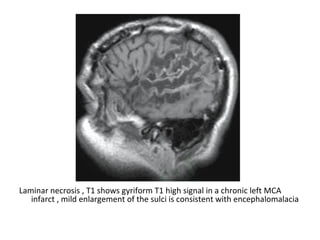

Laminar necrosis , T1 shows gyriform T1 high signal in a chronic left MCA

infarct , mild enlargement of the sulci is consistent with encephalomalacia